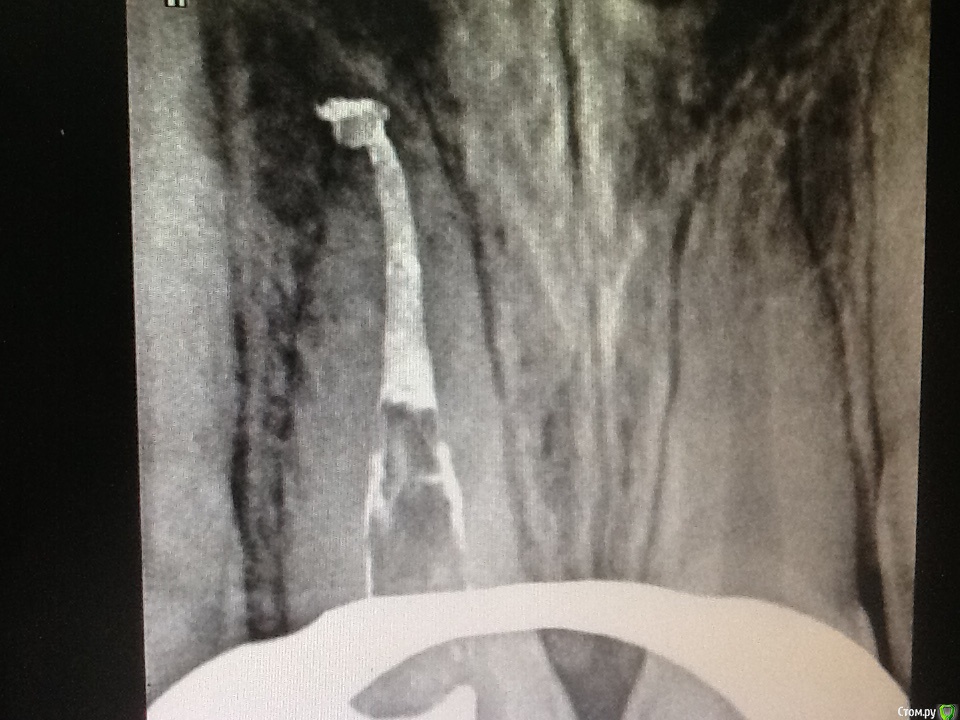

Л Ю С Я Опубликовано 8 октября, 2015 Поделиться Опубликовано 8 октября, 2015 Пациент получил травму в 6 летнем возрасте со вскрытием пульпы. 1.1 Явился в теч 6 часов. Со слов детского стоматолога( коллеги), сделала ампутацию пульпы, закрыли сицем. Ходил год, наблюдался, потом родители забили на это. Появились через 8 лет с просьбой сделать коронку емах, подростка беспокоил внешний вид)))) детский стоматолог начала работу, звонит мне, мол там камень, все ничего не могу сделать. Ссылка на комментарий

Каплан Опубликовано 8 октября, 2015 Автор Поделиться Опубликовано 8 октября, 2015 В мед каналах 3.6 происходит отложение заместит дентина. Ты уверен что воспаление там обратимо? Если потом придётся делать эндо, проблемы могут быть с прохождением каналов. Пульпа в апексе причём будет уже дохлая. Был недавно аналогичный случай у мальчика 14 лет. Травма в 6 лет возрасте, облитерация 1/3 канала, прислали на микроскоп. Я не могу сказать что было очень сложно. Но у детского стоматолога это вызвало проблемы. Могу показать снимок, если интересноДумаешь не стоит уже ждать закрытия апексов и сделать эндо? Ссылка на комментарий